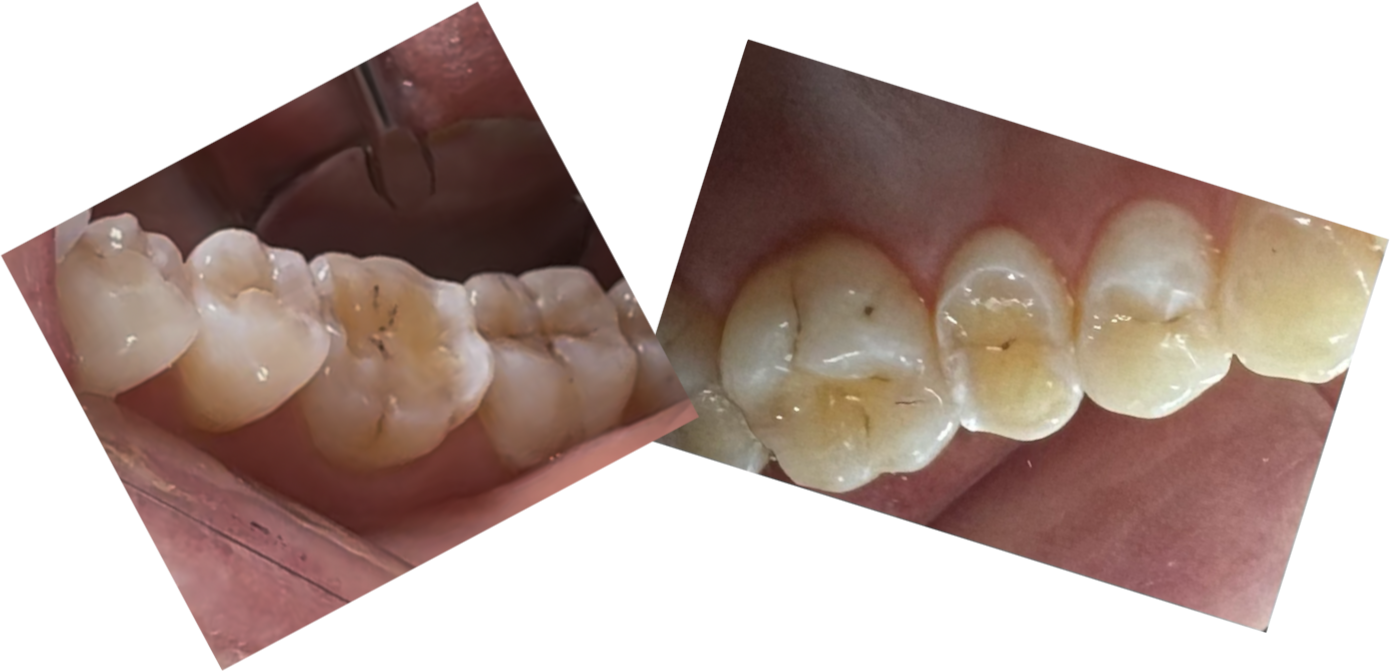

En nøje undersøgelse med gennemlysning afslørede yderligere 5 tænder med revner. Kun de tre tænder fra overkæben er vist her.

Tand der er flækket på langs på grund af en dyb revne

Tænder undersøgt med transillumination